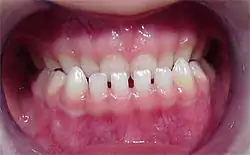

Die Bilder rechts zeigen eine vererbte (hereditäre) Progenie in einer Familie. Der Vater hat die Dysgnathie an die Tochter (im Bild 4 Jahre alt) dominant vererbt.